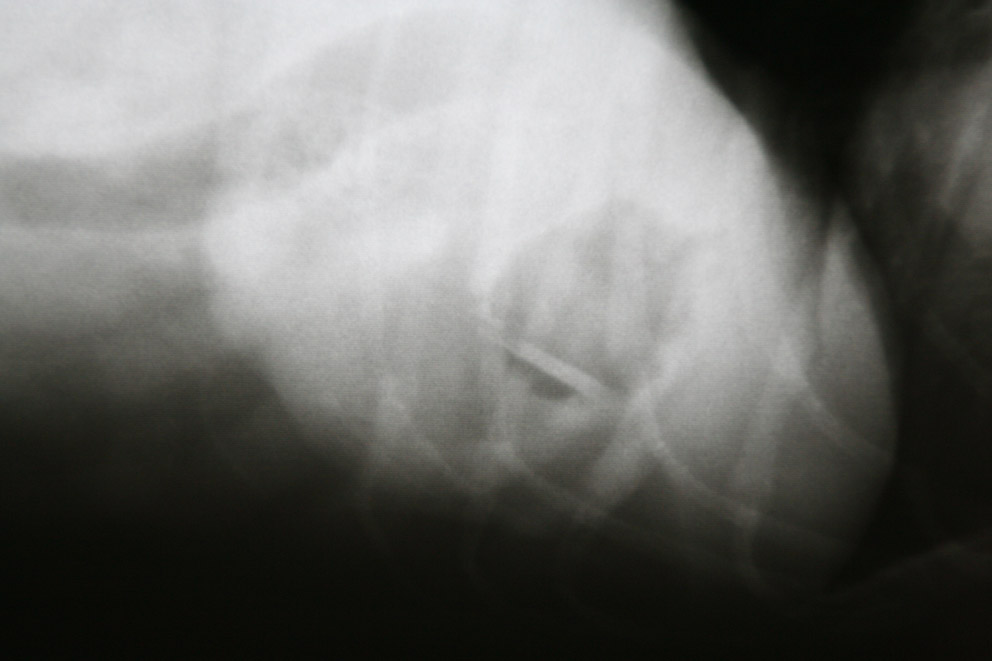

Omdat zo’n vreemd voorwerp zeker wel de oorzaak van de klachten van Fanny zou kunnen zijn en het chronisch braken een reden is voor verder onderzoek, hebben we röntgenfoto’s gemaakt.

en op de andere foto’s wel: